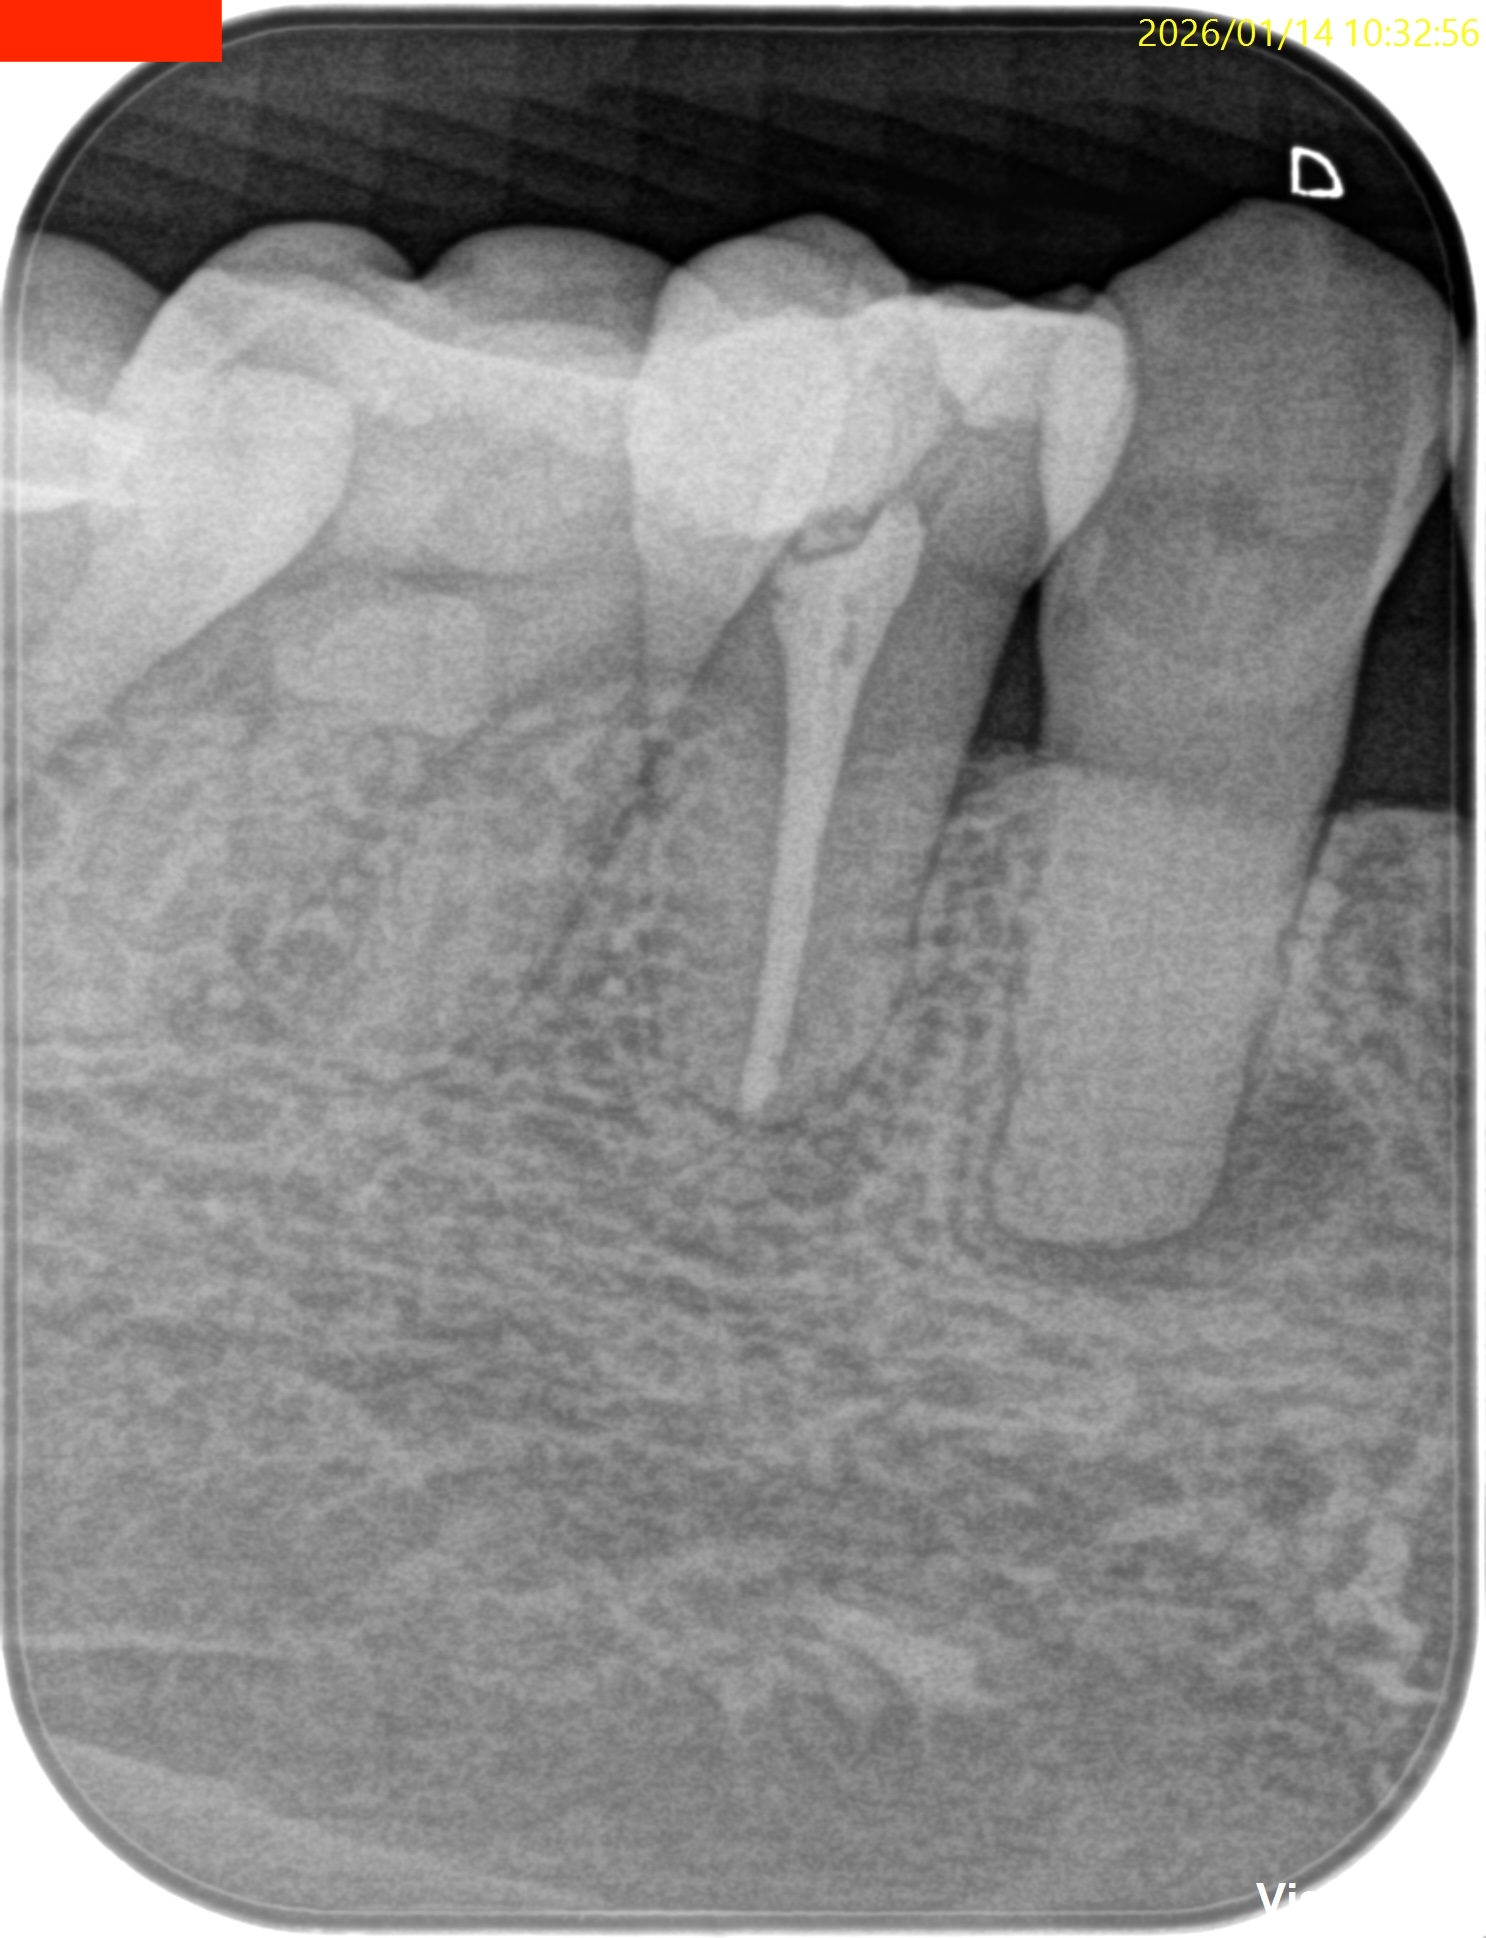

Pre-op Endo test(2026.1.14)

iphoneが就寝前に歯に落ちてきたという。

さておき、外傷が歯に起きると歯髄のある根管が石灰化する。

これで根管治療ができるだろうか?

根管治療だがCBCTによれば、

切端からApexまで約25mmだ。

切端を削れば露髄するはず?である。

が、根管は硬かった…。。。